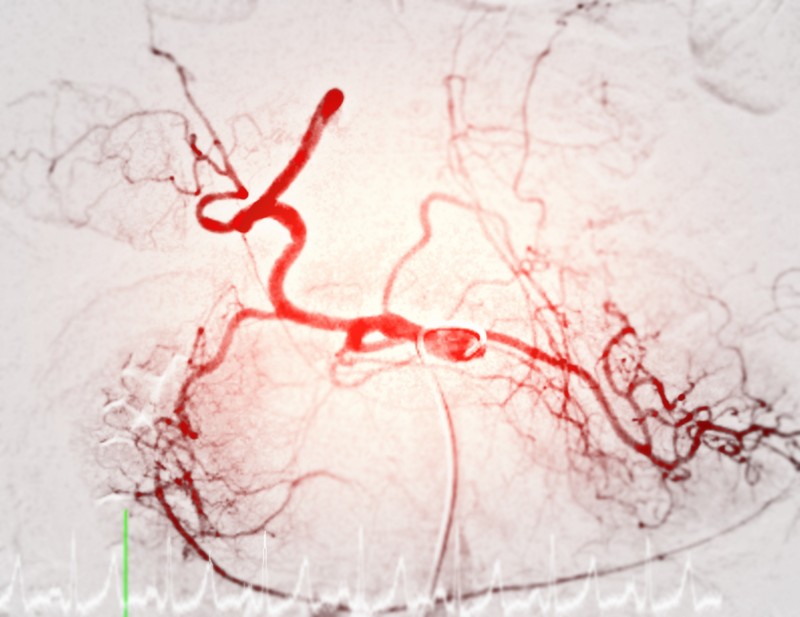

Az arteriográfia egy speciális orvosi képalkotó vizsgálat, amelyet az artériák állapotának felmérésére használnak. Ez a módszer kontrasztanyagos röntgenvizsgálaton alapul, és lehetővé teszi az érrendszer pontos megjelenítését. Az arteriográfiát gyakran alkalmazzák szív- és érrendszeri betegségek diagnosztizálására, érszűkületek vagy elzáródások kimutatására, valamint a stroke és a szívinfarktus kockázatának felmérésére.